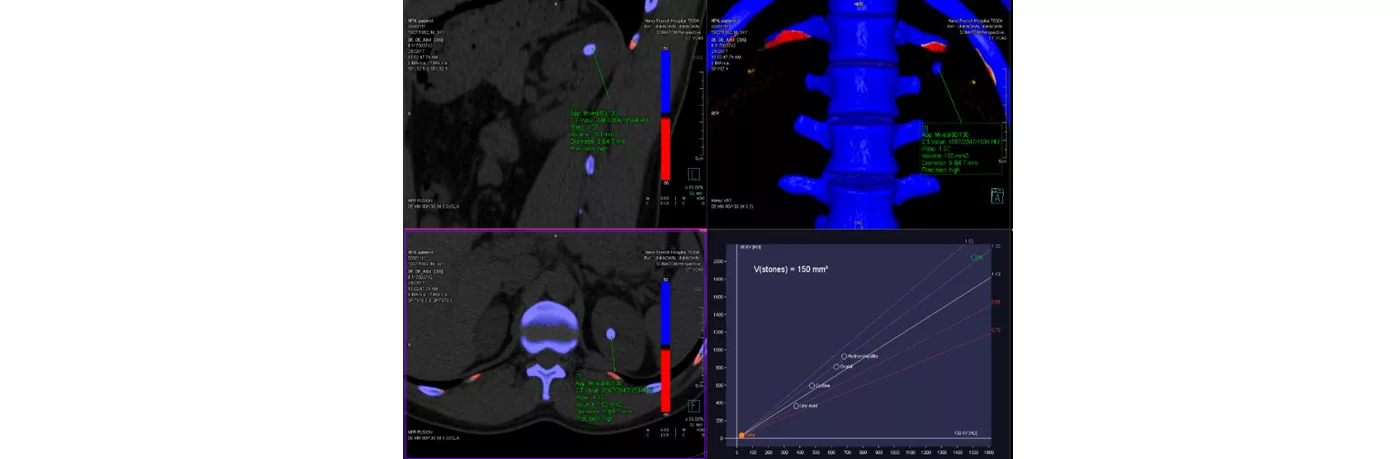

Hình ảnh của phương pháp chụp cắt lớp 2 mức năng lượng đánh giá thành phần sỏi tiết niệu tại Bệnh viện Việt Pháp Hà Nội: